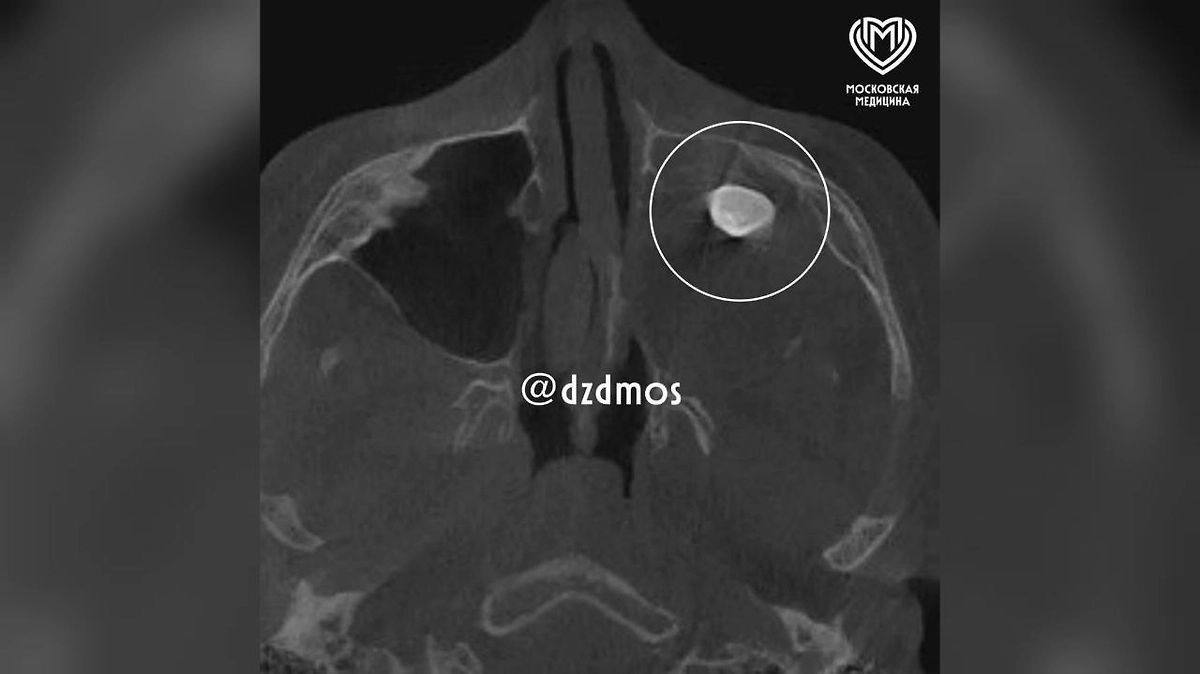

Московские врачи удалили подростку зуб, выросший в носу. Фото © Telegram / Московская медицина

Пациент поступил с жалобами на заложенность носа и асимметрию лица. Ранее его уже осматривали в частной клинике, где обнаружили в гайморовой пазухе сформировавшийся зуб и предложили операцию. Родители решили получить второе мнение и обратились в Филатовскую больницу. Консилиум врачей рекомендовал хирургическое вмешательство по методу Колдуэлла-Люка — доступ через верхнюю десну, чтобы восстановить нормальное дыхание.

В ходе операции хирурги обнаружили не просто зуб, а новообразование, внутри которого он находился. Как пояснил хирург-оториноларинголог Вугар Достиев, это оказалась тератома — эмбрионально-клеточная опухоль, в которой могут присутствовать элементы тканей, нехарактерные для данной области.

«Тератомы очень редко располагаются в зоне лица, чаще в крестцовой области. Ни КТ, ни рентген новообразование не показали, поскольку оно занимало фактически всю левую полость носа. Наша осторожность полностью оправдалась, здесь было важно удалить новообразование единым комплексом, что мы и сделали. Проведение такой редкой и успешной операции стало возможным благодаря работе мультидисциплинарной команды», — сказал он.